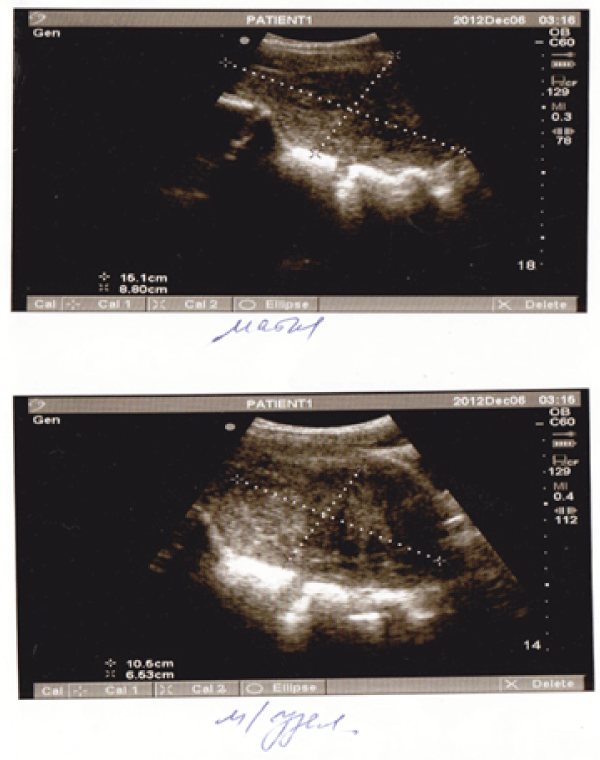

After taking into consideration the clinical picture and ultrasound investigation of the lesser pelvis, including the Colour Doppler scan that marked well pronounced intranodular and perinodular blood flow, a decision was made to perform UAE for the second time. Arteriography and uterine artery embolization were performed in the radio-endovascular surgery department of N.I. Pirogov City Clinical Hospital No.1. An ultrasound investigation showed the uterus to be 6.2cm×3.8cm×5.9cm in size. A wide-stalked tumour mass of heterogeneous echogenicity (12.0 cm×7.0 cm×8.6 cm) had grown out from the posterior wall. It was considered as an interstitial-submucosal fibroid with signs of detachment. The mass was shown as avascular on the Colour Doppler scan.

According to the postoperative ultrasound investigation, the uterus measured 6.0cm×4.4cm×4.8cm. Its borders were regular with no evidence of myomata. Endometrium was 0.8 cm thick with regular and clear borders.

One month after the transcervical myomectomy, an ultrasound investigation of the organs of lesser pelvis was carried out as it had been planned. The uterus measured 6.7cm×4.2cm×5.6cm. Its borders were regular, but the myometrium was heterogeneous. No evidence of myomata. A hypoechoic tumour bed (2.3cm×0.8cm×1.2cm) was revealed on the middle third of posterior wall of the uterus. Thickness of endometrium was 0.5cm on the upper third and 0.2cm on the lower third (Figure 3).

Figure 3: Ultrasound investigation of the uterus after myomectomy (The arrow points to the tumour bed)